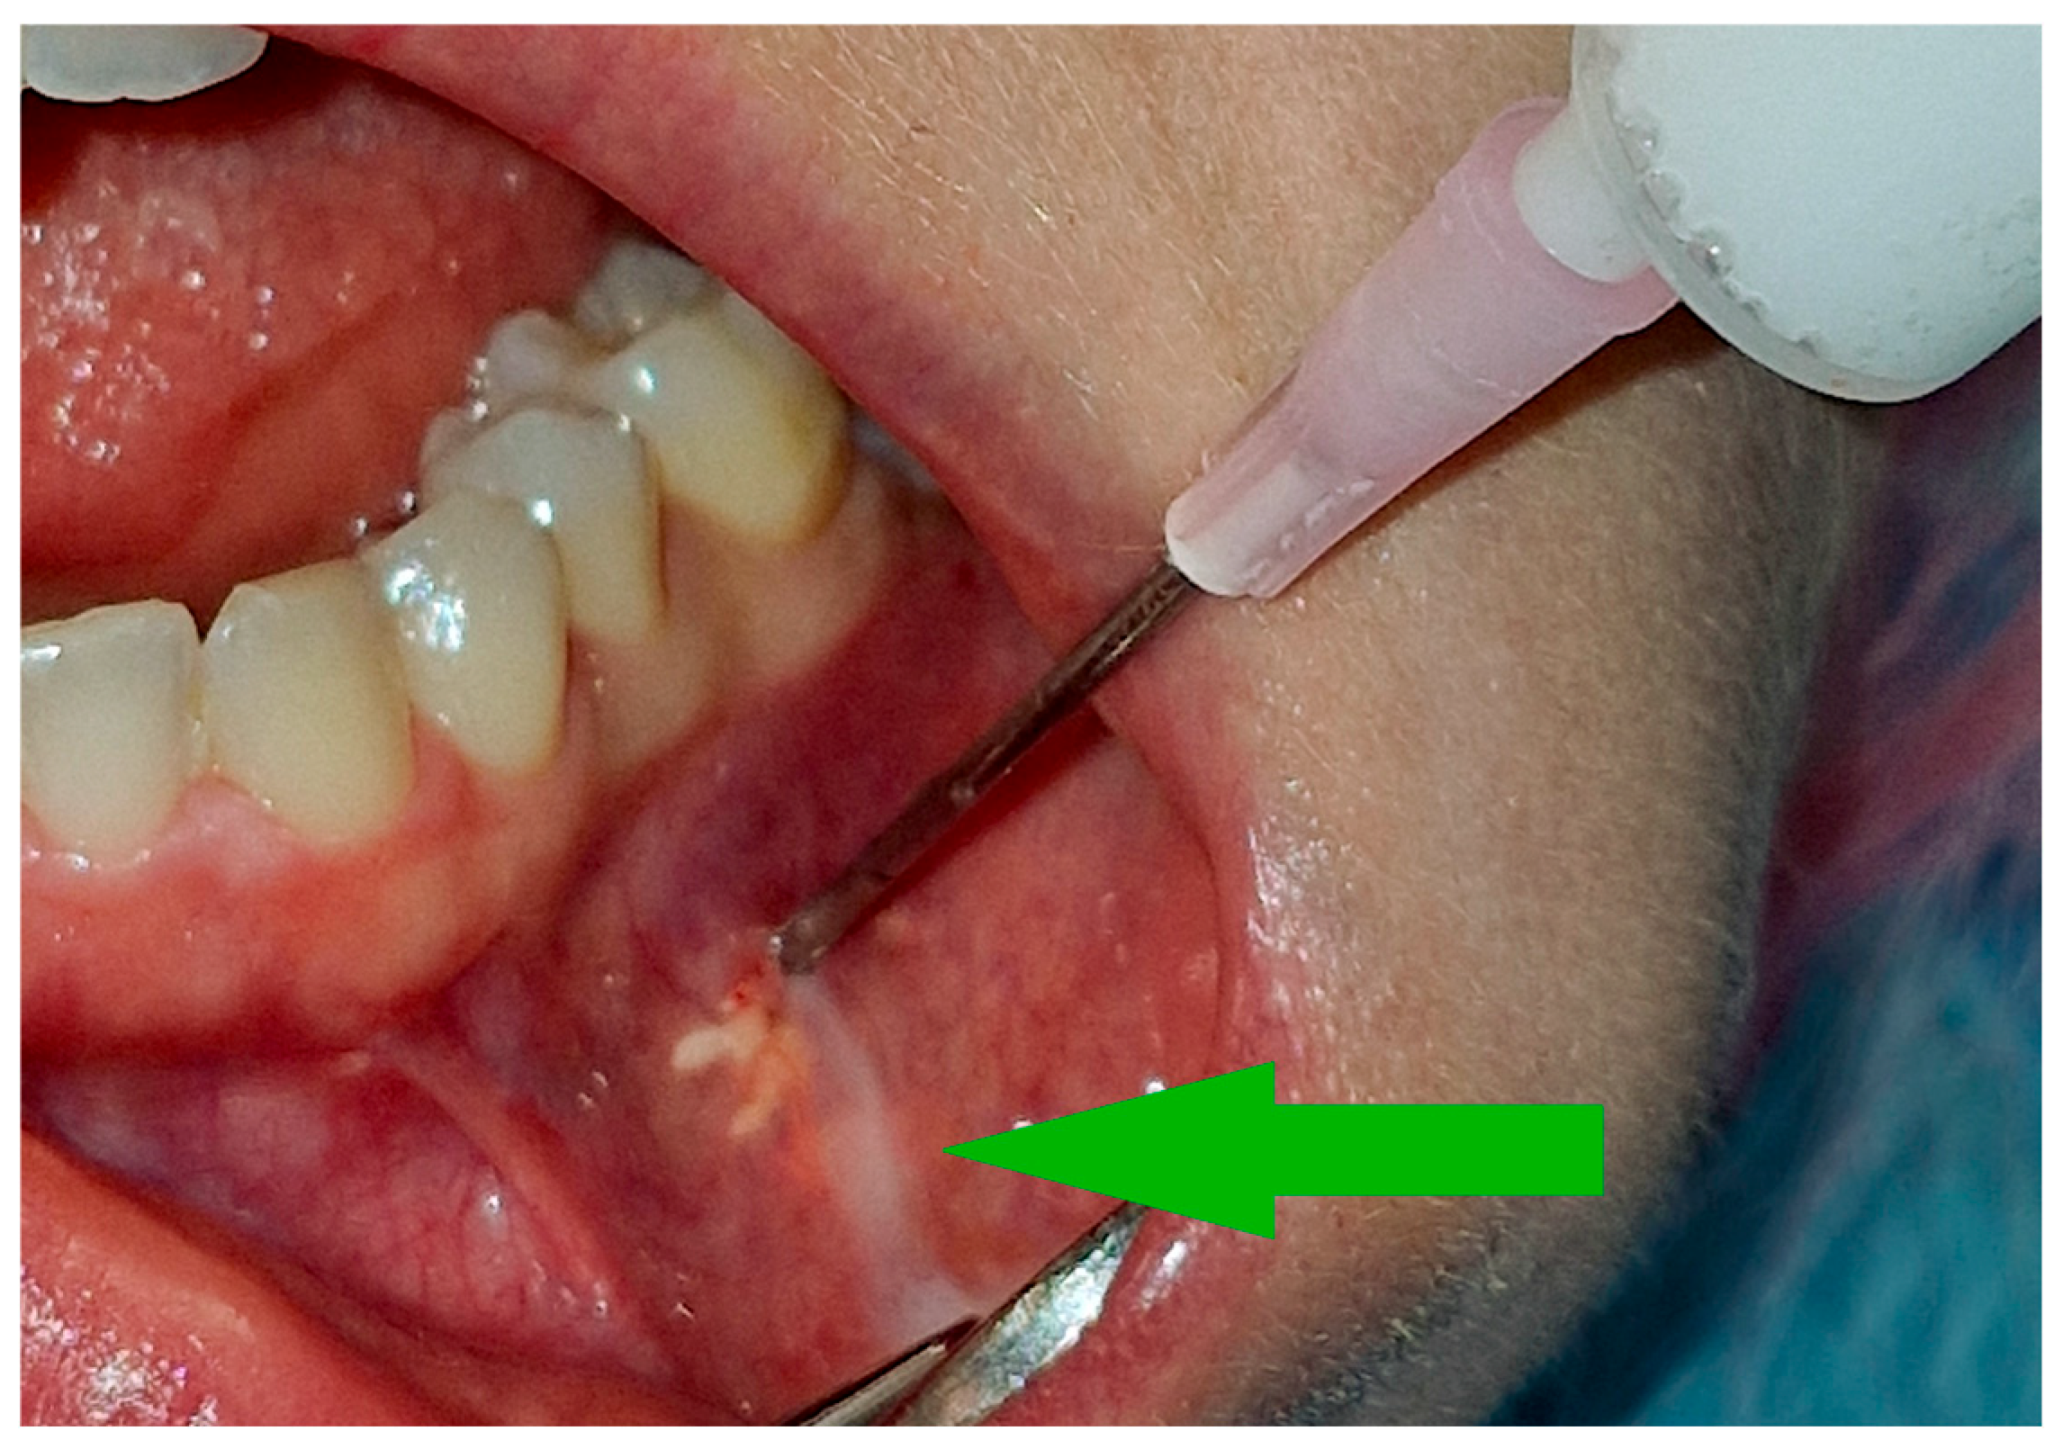

2. Materials and Methods

3.2. Injections